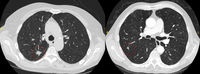

Computed tomography (CT) showing examples of malignant perifissural nodules. Note the spiculated edge of the nodules and the evident retraction of the adjacent fissure. Both resection tissue analyses confirmed adenocarcinoma of lung

From the collection of Dr George Tsaknis, MD, PhD, FRCP(London), MRQA, MAcadMEd, PGCert; used with permission